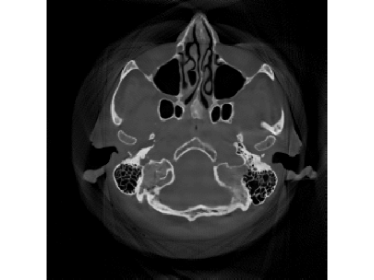

Refer to caption

Figure 9: Reconstruction results for the clinical data (κ=0.6pmax𝜅0.6subscript𝑝\kappa=0.6p_{\max}): (a) ground truth; (b) FBP-WCE; (c) SART-ISD; (d) M1bit-CSR-ISD.

For κ=0.6pmax𝜅0.6subscript𝑝\kappa=0.6p_{\max}, the reconstruction results of FBP-WCE and SART-ISD are given in Fig.9 and 9, respectively. As shown before, the traditional FBP method cannot handle the saturated data. With water cylinder extrapolation, the reconstruction quality has been improved but loss of clear patient boundaries still happens. The overall performance of SART-ISD is slightly better than FBP-WCE but capping artifact can be identified at the object border. Further improvement is obtained using the proposed M1Bit-CSR-ISD to acquire information from the saturated data. As shown in Fig.9, most of outer boundaries are nicely restored and streaking artifacts are effectively eliminated.